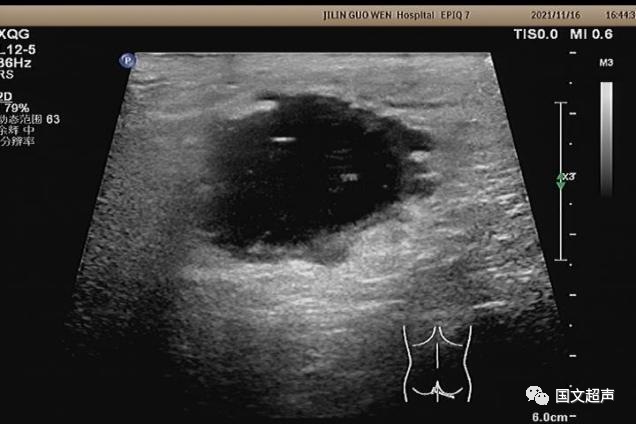

超聲檢查所見:

肛周:7點(diǎn)鐘方向皮下脂肪層內(nèi)探及不均質(zhì)低無回聲包塊,范圍約4.6*3.0cm,較淺處距體表約0.6cm,邊界不清,周圍軟組織回聲增強(qiáng),CDFI:周邊血流信號豐富,輕加壓探頭有涌動(dòng)感,如下圖: